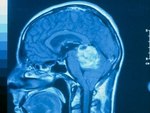

Американских нейрохирургов отстранили от исследований из-за экспериментов над больными

Двум американским нейрохирургам запретили участвовать в медицинских исследованиях из-за экспериментов над умирающими пациентами с опухолями головного мозга. Врачи заносили инфекцию в мозг больных с их согласия. По мнению медиков, это должно было стимулировать иммунный ответ, который приостановит развитие онкологического заболевания. | Все отравившиеся в приморском лагере дети выписаны из больницы

Установлен природный механизм подавления роста опухоли мозга

Международная группа ученых установила механизм, посредством которого клетки-предшественники нейронов подавляют рост глиальных опухолей головного мозга. Они доказали, что предшественники нейронов мигрируют к клеткам астроцитомы и высвобождают вещества, которые являются продуктами метаболизма жирных кислот (эндованилоиды). Эндованилоиды вызывают гибель раковых клеток. | В головном мозге мармозеток нашли ответственную за периферическое зрение область

Американцы предложили лечить опухоли мозга фемтосекундным лазером